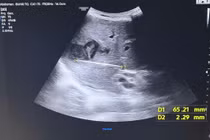

Qua siêu âm ổ bụng, các bác sĩ ghi nhận gan của ông T. to bất thường. Tại thùy gan phải xuất hiện vùng tổn thương lớn sát bao gan, gồm nhiều nang nhỏ kèm viền thâm nhiễm rộng xung quanh. Hai tổn thương chính có kích thước lần lượt 52×88 mm và 25×32 mm. Ngoài ra, bệnh nhân còn có tình trạng dịch ổ bụng và dịch màng phổi.

Ổ áp xe chiếm gần trọn gan phải đẩy người bệnh vào cơn nguy kịch - Ảnh BVCC

Bệnh nhân được siêu âm kiểm tra lại, kết quả ghi nhận tổn thương tại hạ phân thùy 7 tăng kích thước từ 25×32 mm lên 50×80 mm và đã chuyển sang giai đoạn hóa dịch. Dựa trên hình ảnh siêu âm cùng các chỉ số xét nghiệm, bác sĩ xác định đây là thời điểm thích hợp để tiến hành chọc hút ổ áp xe gan dưới hướng dẫn của siêu âm.